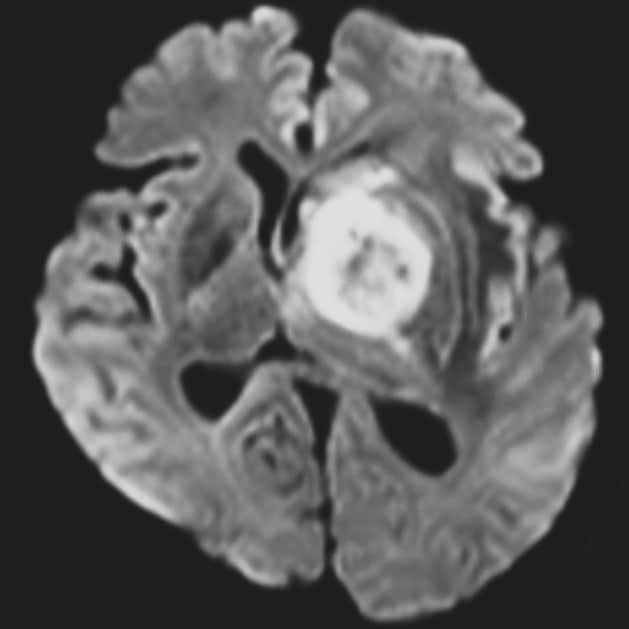

認知機能低下、行動異常、右不全片麻痺の進行を認め、頭蓋内の精査目的に頭部MRIが施行された。左大脳基底核に腫瘍性病変および腫瘍周囲浮腫の所見を認めた。同病変は、造影T1強調像画像では極めて淡い軽度の造影効果を示し、拡散強調画像では軽度の高信号、ADC画像では低信号を示した。診断確定のため生検手術を行った。生検手術1週間後に頭部MRIを施行すると、術前に施行した頭部MRIとは所見が変化し、左大脳基底核の病変は造影T1強調画像では明瞭な造影効果を認め、拡散強調画像でも高信号の増強、ADC画像では低信号を示した。病理組織学的診断は中枢神経系原発悪性リンパ腫であった。そのためR-MPV療法(リツキシマブ、メトトレキサート、プロカルバジン、ビンクリスチン)を施行した。R-MPV療法の経過中の頭部MRIでは、左大脳基底核の病変は縮小傾向を認め、それに伴い初診時に認めていた認知機能低下、行動異常、右不全片麻痺は改善傾向にあり、良好に経過している。

非造影PCNSLにおいては、拡散強調画像での高信号やADC値の低下が有用とされているが、画像的診断は困難である場合が多い。そのような症例においては、生検手術によって血液脳関門の破綻・血管新生・免疫応答などの複合機序が作用し、造影所見が明確になることが多いとされている。そのため、非造影PCNSLの診断に関しては、生検手術のタイミングと術後造影MRIの再検査による統合的評価が重要である。